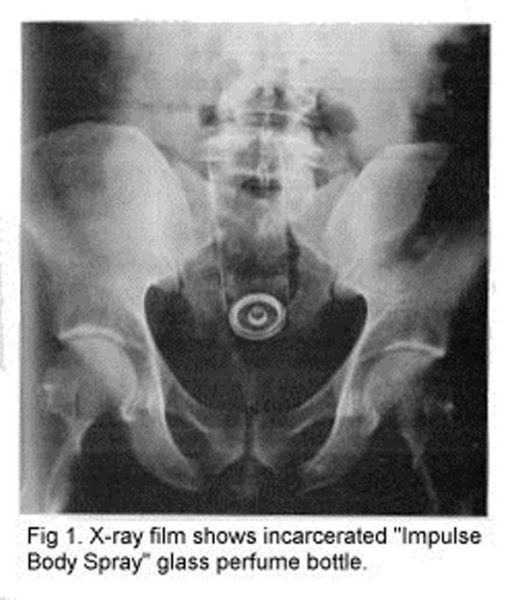

Impulse Body Spray